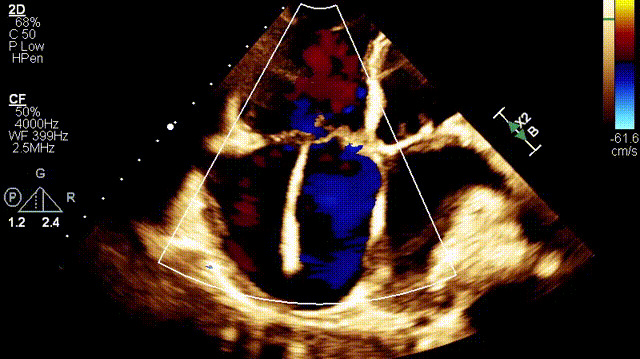

接受治療的是一例89歲的超高齡女性患者,主訴“起搏器術(shù)后7年余,反復(fù)氣促4年”,因反復(fù)心衰失代償,胸腔積液就診。術(shù)前超聲提示:1.雙房及右室擴(kuò)大(右室舒張末和收縮末容積分別為55ml和21ml,右室FAC27%);2.三尖瓣瓣環(huán)擴(kuò)張(瓣環(huán)左右徑41mm,前葉長(zhǎng)度21.3mm,隔葉長(zhǎng)度15.2mm,后葉長(zhǎng)度23.1mm),瓣葉閉合不攏;3.功能性重度三尖瓣反流(FTR 5+,收縮期三尖瓣口反流束縮流頸寬度21mm);4.下腔靜脈內(nèi)徑約25mm,呼吸塌陷率<50%;5.輕度肺高壓。術(shù)前CT結(jié)果顯示,入路血管最小平均徑約9.6mm,入路血管無(wú)嚴(yán)重迂曲、鈣化。隨后,王焱教授及其團(tuán)隊(duì)王斌教授、陳翔教授、超聲科蘇茂龍主任、手術(shù)室溫紅梅護(hù)士長(zhǎng)進(jìn)行了詳細(xì)而周密的術(shù)前討論,最終選擇我國(guó)自主研發(fā)的LuX-Valve Plus經(jīng)血管三尖瓣置換系統(tǒng)對(duì)患者進(jìn)行手術(shù)。

術(shù)后超聲